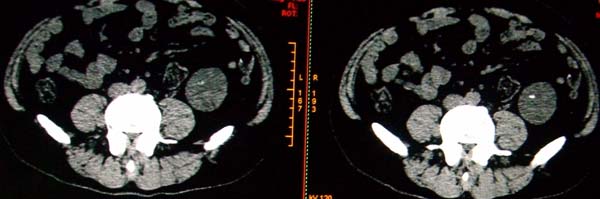

标题: CT17174:M38Y,体检超声提示右肾发育不良,病人无明显不适 [打印本页]

标题: CT17174:M38Y,体检超声提示右肾发育不良,病人无明显不适

右肾发育不良;考虑左肾下极血管平滑肌脂肪瘤可能,建议增强。

右肾微小发育不良  左肾下极错构可能

1)左肾下极占位性病变,不排除肾癌可能;建议行进一步检查。2)右肾发育不良。

左肾下极占位性病变,不排除肾癌可能;建议增强及明确内部组织ct值。右肾发育不良。

右肾发育不良。左肾下极占位。

右肾发育不良。左肾代偿。左肾下极占位,性质待定,建议强化。

右肾发育不良

右肾发育不良。左肾下极占位。建议增强!

右肾发育不良。左肾下极占位。  强化

右肾发育不良。左肾下极囊实性占位,建议增强。